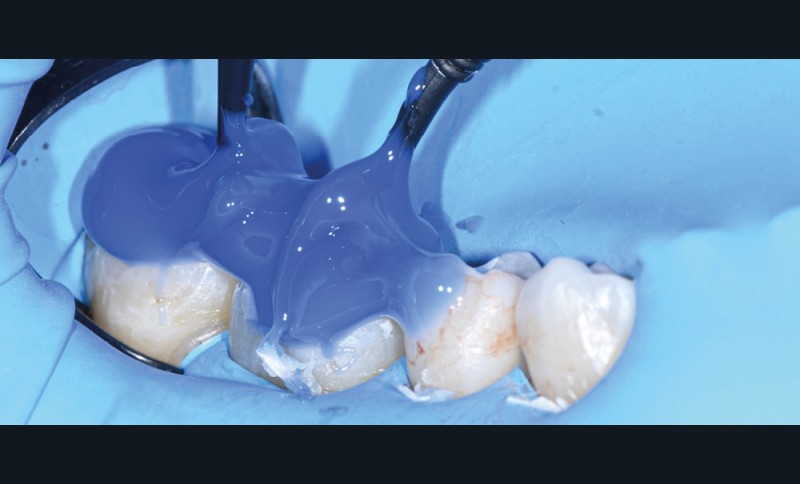

La « stamp technique », ou tampon occlusal, est une technique très intéressante à maîtriser lors de séances de restaurations directes. La première étude décrivant cette technique que nous avons retrouvée date du milieu des années 1990 [1]. Depuis, les matériaux et les principes ont évolué pour aboutir à un procédé très fiable en pratique quotidienne [2-5].

Nous détaillons la technique à travers le cas d’une jeune fille de 18 ans présentant des lésions carieuses sur quatre dents (fig. 1 à 14).